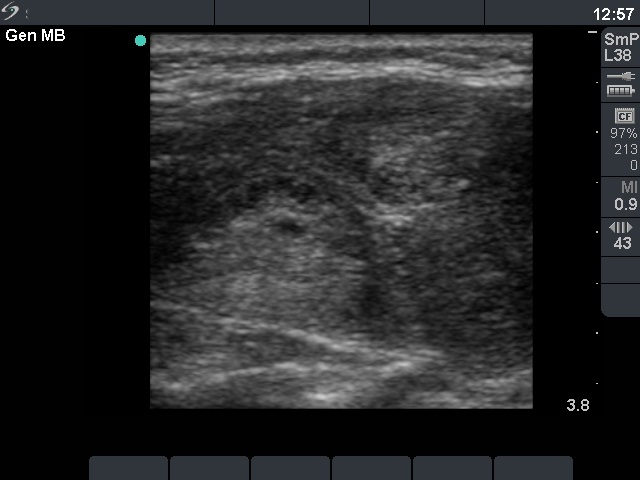

Ultrasonography: the thyroid was hypoechogenic with two well-circumscribed hyperechogenic areas in the right lobe. These were surrounded with a halo and presented perinodular blood flow.

Comment: it was unequivocal that the patient had Hashimoto's thyroiditis. The sonographic picture was equivocal whether the patient had nodule or nodules, too. However, the cytology was more problematic. It became evident after histopathology that the lesion in question was a focus with proliferation of oxyphilic cells. What did we do wrong? I think that such cytological picture itself is almost identical with that seen in a Hürthle-cell tumor. Although there were signs which disfavor the possibility of tumor, we could not exclude the presence of tumor with enough safety. Two minor signs were remarkable: firstly, the presence of nuclear debris which was suspicious for the presence of lymphocytic infiltration even within this lesion ; secondly, the lack of prominent nucleoli decreased the possibility of a Hürthle-cell tumor. The US appearance of the 'nodules' were remarkable. In contrast with a real nodule, these were irregular. Circumscribed areas were also found in the left lobe. Moreover, a follicular tumor is solitary in most cases.